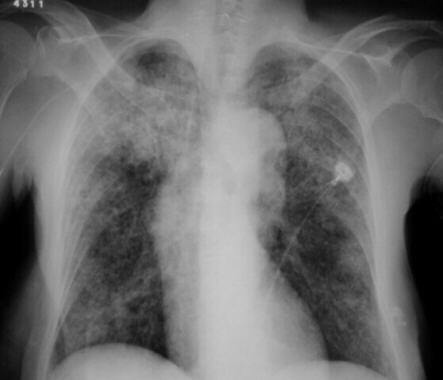

Chest X-Ray demonstrating bilateral diffuse pulmonary micronodular infiltration (miliary lesions).